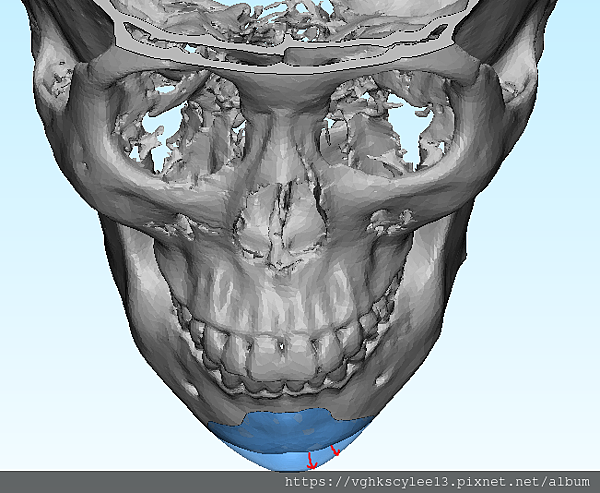

下圖:不對稱下巴骨架,透過列印技術可以做出調整下巴歪斜的假體組合。

歪斜下巴調整性假體設計

下圖範例:歪斜不對稱下巴經3D導航客製化導航矯正性假體

(下圖)3D模擬後工程師版的設計下巴假體的外型。

經過李醫師醫師對客戶外型的判斷,修改工程師的設計,建議更改後的假體模型(下圖)

(上圖)經過李醫師醫師對客戶外型的判斷,修改工程師的設計,建議更改後的假體模型。所以嘍,醫師的美感與專業度必須要做判斷,3D列印只是精準工具但是必須有專業醫師的判斷才可以完美!

下圖: 在李醫師確認後完美精準例印

窄小後縮的下巴,以精準3D列印技術來客製化醫師判斷後的外型下巴假體,一起改善嘴形相對的狀態。

窄小後縮的下巴,以精準3D列印技術來客製化醫師判斷後的外型下巴假體,一起改善嘴形相對的狀態。

3D模擬後 列印出吻合的設計下巴假體